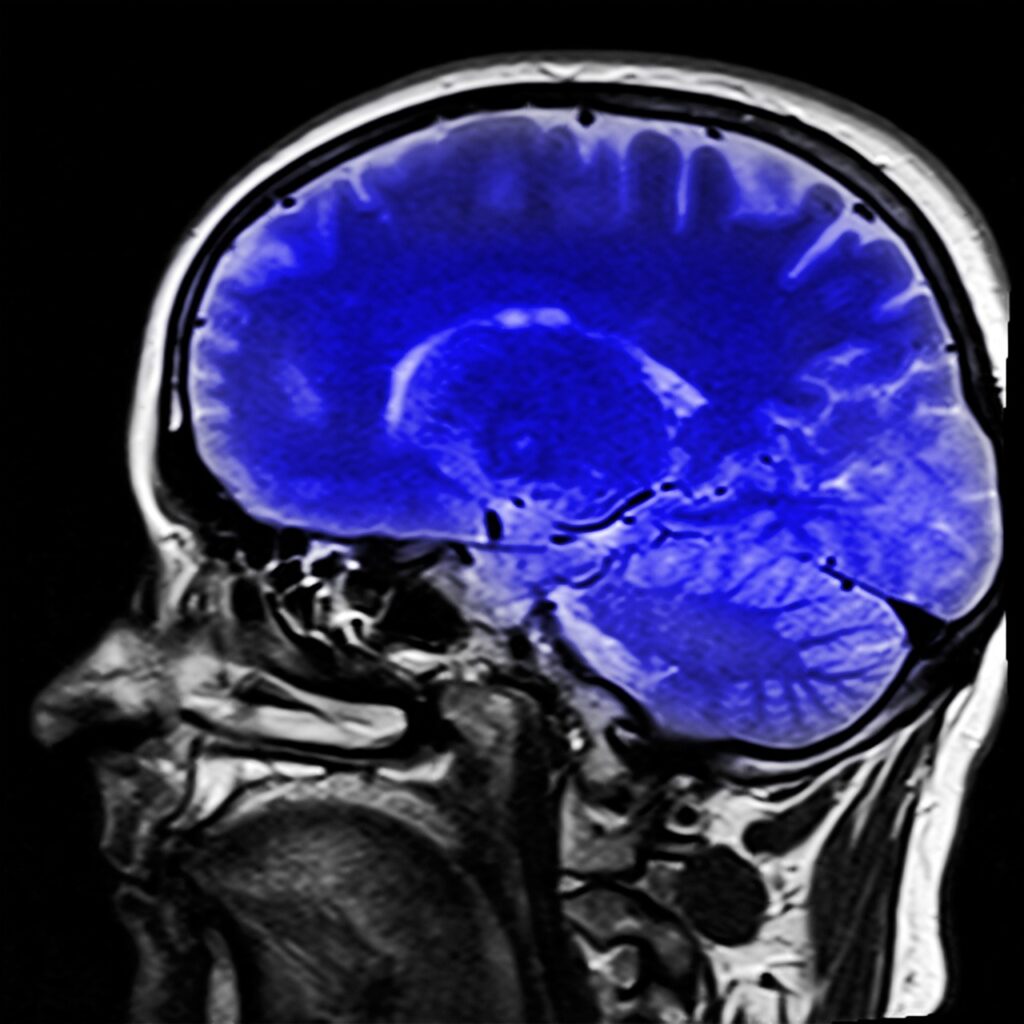

La SLYM resultó ser una máquina difícil de descifrar. Ahora, gracias a los avances en neuroimagen y biología molecular, investigadores de EEUU y Dinamarca han descubierto una nueva estructura en el cerebro.

Lo llamaron SLYM, que es la abreviatura de tipo linfoide subaracnoideo. Los científicos describen al SLYM como un componente previamente desconocido de la anatomía del cerebro, el cual actúa como una barrera protectora y una plataforma para monitorear la inflamación y la infección.

Cuarta Meningitis. El cerebro está cubierto por tres membranas llamadas meninges: la piamadre, el material aracnoideo y la duramadre. Estas membranas forman una barrera entre el cerebro y el resto del cuerpo.

Entre la piamadre y la aracnoides hay un espacio llamado espacio subaracnoideo, que está lleno de líquido cefalorraquídeo que fluye dentro y alrededor del cerebro y ayuda a amortiguarlo y proporcionar nutrientes. La nueva estructura recién descubierta será la cuarta membrana ubicada en el espacio subaracnoideo por encima de la piamadre interna.

Como explican los investigadores, la función de la membrana SLYM va más allá de cubrir el cerebro para ayudar a controlar el flujo de líquido cefalorraquídeo dentro y fuera del cerebro. Nuestra hipótesis es que SLYM actúa como una barrera entre el líquido cefalorraquídeo ‘limpio’ que ingresa al cerebro y el líquido cefalorraquídeo ‘sucio’ que sale, llevándose las proteínas de desecho, explicó el Dr. Virginia Plá Requena, uno de los autores del estudio e investigadora del Centro de Neuromedicina Traslacional de la Universidad de Copenhague.